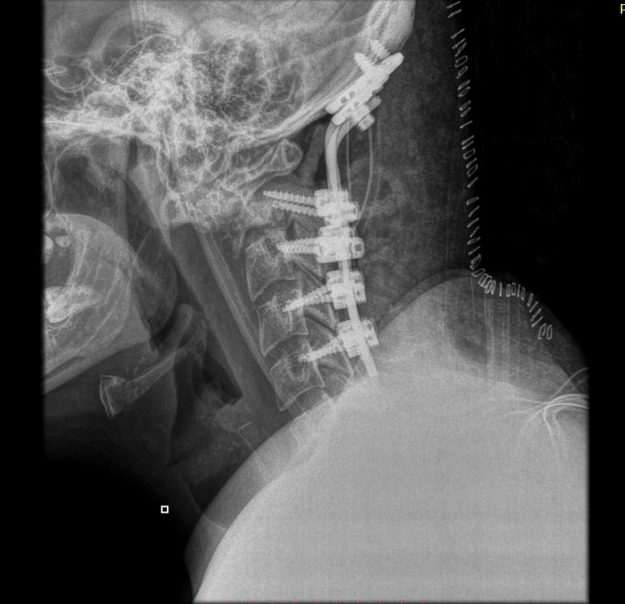

Νεαρή ασθενής 17 ετών με εκτεταμένη συριγγομυελία από την αυχενοπρομηκική συμβολή έως το τελικό τμήμα του νωτιαίου μυελού, λόγω συνδρόμου Chiari. Κλινικά αιμωδίες (μουδιάσματα) άνω άκρων, ζάλη. Αφού ο εργαστηριακός έλεγχος απέκλεισε συνοδά προβλήματα (πχ καθηλωμένο τελικό νημάτιο κ.α.) αποφασίστηκε η επέμβαση αποσυμφόρησης του οπισθίου κρανιακού βόθρου με ανάδυση των αμυγδαλών της παρεγκεφαλίδας και μηνιγγοπλαστική.…